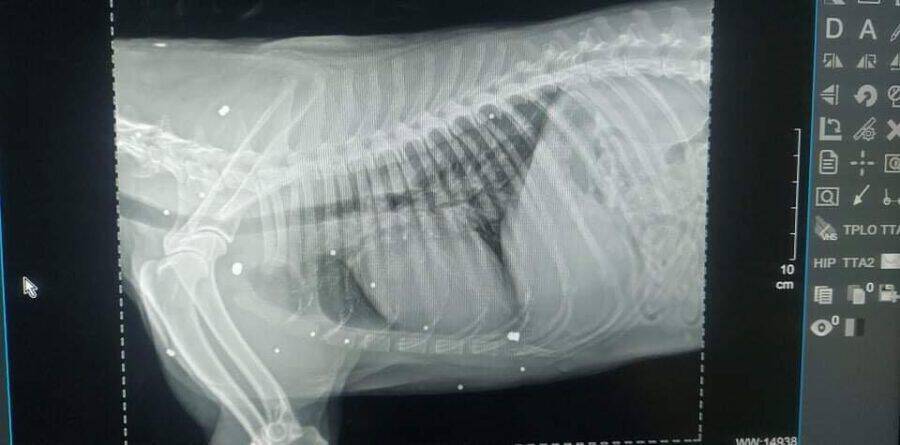

Leider hat Henry ein paar gesundheitliche Baustellen. Zum einen ist es ein Tumor am Hals, den wir im Oktober 2021 entfernen ließen und zudem hat eine Augenentzündung. Bei weiteren Untersuchungen konnte man auf den Röntgenbildern sehen, dass er einen alten Bruch am Hinterbein hat und eine Pfote etwas schief steht. Außerdem haben wir mit Erschrecken festgestellt, dass sein ganzer Körper voll mit Schrotkugeln ist. Auf ihn wurde also geschossen! Das Auge wurde bisher nicht operiert, da es recht schwierig ist und wir warten möchten, bis er sich mehr an den Umgang mit Menschen gewöhnt hat.